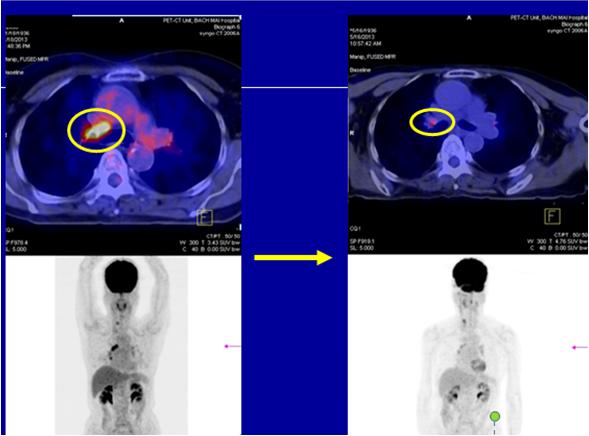

* SO SÁNH TRƯỚC VÀ SAU ĐIỀU TRỊ 30 THÁNG

Trước điều trị

- Ho, đau ngực

- U phổi phải nhỏ thùy dưới di căn hạch trung thất lớn (KT 2x4cm, max SUV 12,6), di căn 2 phổi; CEA 75,6

Sau điều trị:

- Hết ho, hết đau ngực

- Không còn rõ u

- CEA: bình thường (4,5ng/ml)

Hình 3. Hình ảnh PET/CT toàn thân trước và sau điều trị